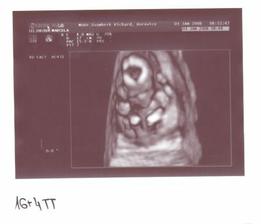

Jako v pohádce. 1.9.2007 jsme měli svatbu. 18.9.2007 jsme odjeli do Egypta na svatební cestu. Ze které jsme přijeli ve třech. Opravdu se nám to povedlo. 7.10.2007 jsem nedostala MS 10.10.2007 HURÁ !!!! Těhoteský test pozitivní. 12.11.2007 první KO, jsem 9+1 tt. Pan doktor mi dělal UTZ, dal mi první fotku mimíška. Těhotenství potvrzeno na 100 %,dostala jsem Těhotenskou průkazku. 29.11.2007 11+6 tt Byla jsem na odběru krve. Mám nízký tlak. 10.12.2007 13+3 tt KO viděla jsme opět mimíško na UTZ, má se čile k světu. Krev je vpořádku. 13.12.2007 potvrzení od obvodní lékařky a měření EKG. 3.1.2008 16+4 tt KO odběr krve na Triple test. UTZ mimíšku pěkně bije srdíško. Mám stále nízký tlak. Berou mě křeče do lýtek a pálí žáha. Pan doktor mi napsal MagneB6. 19.1.2008 18+6 tt už se pomalu do ničeho nevejdu. První nákup těhu kalhot a těhu blůza. 22.1.2008 19+2 tt dnes ráno jsme cítila jak mě mimíško několikrát koplo. A dopoledne v práci jsem cítila takové šimrání v bříšku. 28.1.2008 dneska jsem koupila mimíškovi první bodíčka. 31.1.2008 20+4 tt KO Trile test nagativní. Pan doktor mi dělal UTZ a pravděpodobně to bude KLUK. Poznala jsme to i já. Mimíško už váží 400g. Manžel měl radost. 4.2.2008 21+1 tt první těhotenské plavání. Bylo to moc pěkné a myslím, že i mimíšku v bříšku se to líbilo. 9.2.2008 – 16.2.2008 mám dovču. Jeli jsme na hory, ale já jsme raději nelyžovala, abych neublížila mimíšku. Vynahradím si to až příští rok. Hodně jsem odpočívala a chodila na procházky. 18.2.2008 kontrola u zubaře. Vše v pořádku. 19.2.2008 v práci mi bneska hodně tvrdlo a bolelo břicho. Tak uvidím jak mi bude zítra. 20.2.2008 23+3 tt opět mě tvrdlo a bolelo břicho až do zad. A docela intenzivně. Popráci jsem šla rovnou k doktoru. Vyšetřil mě a říkal, že to není moc dobré. Raději mi napsal neschopenku. 21.2.2008 bolí mě v kříži, především při chůzi. Jen doufám, že to nebude až do konce těhulkování. 27.2.2008 24+3 tt dneska jsem šla k obvodní doktorce s tou bolavou kyčlí. Stále mě dost bolí. Poslala mě na těhotenské cvičení, kde mi ukážou nějaké uvolňovací cviky a mám odpočívat. Snad to přejde. 5.3.2008 25+3 tt těhotenaké cvičení v nemocnici. Sestřička mi ukázala nějaké cviky na uvolnění kyčle a masáž. 10.3.2008 26+1 tt dneska jsme byli s manželem na 4 D UTZ. Bylo to moc hezké, mimíško se nám hezky ukázalo. Dokonce jsme viděli, že je to opravdu kluk. Pan doktor nám udělal nějaké fotky a nahrál mimíško na DVD. Je to opravdu moc krásný a jedinečný zážitek. 11.3.2008 26+2 tt dnes jsem byla v nemocnici na testu na cukrovku. 13.3.2008 začala jsme chodit do Solné jeskyně. Moc pěkně se tam relaxuje. Rozhodně to všem doporučuji. 19.3.2008 Dnes velký nákub oblečků na mimíško. 20.3.2008 27+4 tt KO test na cukr mám v normě. Tlak stále nízký a žáha mě pořád pálí. Bolest kyčle už ustoupila. Parvděpodobně mimíško změnilo polohu a netlačí už na nic. 29.3.2008 Byli jsme se podívat na kočárek. Nakonec se nám nejvíce líbí kočárek JANE SLALOM PRO, barva hnědooranžová. 10.4.2008 začala jsme chodit na těhu cvičení na Gymbalonech. 16.4.2008 první hodina předporodní přípravy. 17.4.2008 31+4 tt KO UTZ mimíško podle měření už váží 2100g, doufám, že to nebude žádný obřík. Jinak se má k světu a vše je v pořádku. Byla mi odebrána krev. 25.4.2008 32+5 tt pěkně mě bolí v krku. Návštěva obvodní lékařky. Udělala mi výtěr a uvidí podle výsledků. 28.4.2008 výtěr je vpořádku, ještě mě pro jistotu poslala na krční. Prý v těhotenství bývají zduřelé krční mandle. Tak by to mělo přejít samo. Mám brát pouze těhu vitamíny. Dneska jsme si přivezli kočárek. Nechali jsme ho u rodičů, pro jistotu, pověra je pověra, ale kdo ví. 4.5.2008 34 tt nástup na mateřskou dovolenou. Začínám s masáží hráze. 5.5.2008 34+1 tt KO UTZ mimíško už tam nemá moc místa, váží už 2500g, Mám nízké hodnoty železa v krvi. Tak jsem dostala vitamín železo. Magnesium už nemám brát. Dneska jsme byli s manželem v nemocnici, kde budu rodit, na předporodní besedě. Řekli nám, co nás čeká při porodu, a ukázali porodní pokoj. 8.5.2008 doma generální úklid a příprava na mimíško. Oblečky na mimíško mi pere a žehlí mamka, je moc hodná a hodně mi s tím pomáhá. Jsem moc ráda a tato práce mi odpadla a já si domů odvezu už vše hotové. 9.5.2008 34+5 tt celou noc jsem nespala, mám rýmu a strašný kašel. Docela se bojím i o mimíško. Tak jsem raději šla k obvodní doktorce. Ta mě poslechla, mám zánět průdušek. Dala mi antibiotika ZINNAT 250mg. Moc nejsem nadšená. Ujišťovala mě, že se můžou v těhotenství, a i v lékárně mi to říkali. Doma jsem si to našla i na Internetu. Tak snad bude vše vpořádku. 12.5.2008 35+1 tt Dneska jsem byla na natočení na EKG, to prý potřebuji k porodu. 13.5.2008 Opět mě začal bolet kyčel, jak mě již jednou bolel. Asi se mimíško nějak jinak uvelebuje a tlačí mi na nějaký nerv. 15.5.2008 35+4 tt KO doktor říkal, že mě ta kyčel pravděpodobně přestane bolet až po po porodu. Tak nejsem moc šťastná, protože je to dost omezující, především při chůzi. Mimíško je vpořádku. Dneska mi poprvé natáčel monitor, tak jsem slyšela tlukot mimíškova srdíčka. 26.5.2008 37+1 tt Dneska mám narozeniny!!! KO pan doktor mi dělal vyšetření a kultivaci z pochvy. Od příštího týdne už budu chodit na KO do nemocnice, kde také budu rodit. Tak už jsme se rozloučili a mám k němu přijít na KO až po šestinedělí. Snažím se, co nejvíce odpočívat. 2.6.2008 38+1 tt KO už v nemocnici. Výsledky kultivace nejsou moc dobré, tak jsem dostala globule na zavádění. S paní doktorkou jsme se domlouvali na průběhu porodu, protože jsem v minulosti měla zlomenou sedací kost. Domluvili jsme se, že porod necháme přírodní cestou a pokuď bude něco špatně, tak přistoupí k císařskému řezu. Doufám, že bude vše bez komplikací. Opět mi natáčeli monitor. 9.6.2008 39+1 tt KO natáčení monitoru. Je moc hezké slyšet jak mimíšku bije srdíčko. Dneska mi dělala vyšetření, vše je vpořáku. Zítra jdu na UTZ. 10.6.2008 39+2 tt dneska jsem byla na UTZ, kde měřili mimíško. Podle měření váží asi 3509g. Nakonec jsme se s paní doktorkou domluvili, že pokud neporodím do 22.6., tak si v pondělí 23.6. v 8 hodin půjdu lehnout do nemocnice, abych moc dlouho nepřenášela a mimíško nebylo moc velké, vzhledem k té zlomené sedací kosti. No nějak mi to těhulkování moc rychle uteklo a už se ten obávaný porod opravdu blíží, což si nějak moc nechci připouštět. Ale můžu říci, že jsem si to moc užila a ještě užívám. Je to asi opravdu ta nejkrásnější doba v mém životě. Vědět, že v sobě máte mimíško, a těšit se na něj. 16.6.2008 40+1 tt tak dneska už jsme byla na natočení monitoru a na poslední KO. Doktorka mi dělala vyšetření a říkala jak miminko je hezky sestouplé. Prý je dobře připraveno k porodu a vše vypadá, že bych mohla porodit dříve než v pondělí. Aby mi nemuseli porod vyvolávat. Já bych raději chtěla porodit normálně bez vyvolání. Doufám, že se to povede. Jinak v pondělí 23.6.2008 nastupuji do nemocnice. No tak musíme doma zkusit osvědčené babské rady, snad se nám to povede. Mimíško se nějak v bříšku zabydlelo a vůbec se mu nechce ven. Držte nám palečky. Děkujeme. 17.6.2008 40+2 tt od 23.00 hod tvrdnutí bříška, že by to již bylo ono???? Ve 23.43 hod začínají kontrakce po 10 minutách. 18.6.2008 40+3 tt ve 2.30 hod odjezd do porodnice. Kontrakce po 4,5 minutách. V 8.29 hodin DAVÍDEK na světě. Váží 3880g a měří 52 cm. Tatínek byl u porodu a byl moc velkou oporou mamince. Moc si toho vážím. Je to velká odměna a stálo to za to. Těď už jsem ne dva, ale tři. Jedna velká rodina. Jsme moc šťastni.